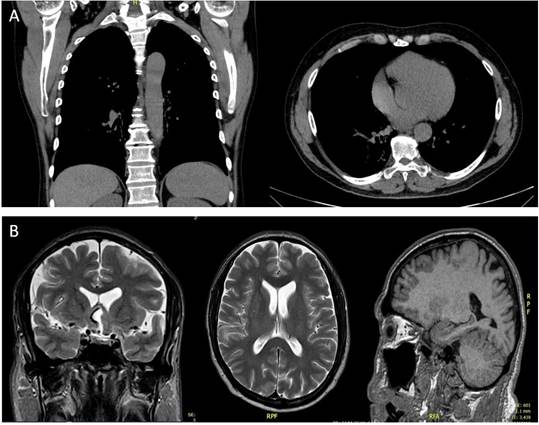

En los resultados imagenológicos de Rx de tórax se evidencian micronódulos (Fig. 3a), además en RNM de cráneo presenta zonas hipodensas de predominio cerebral anterior y celulitis preseptal (Fig. 3b).

Las transaminasas hepáticas salen dentro de parámetros aún normales, por lo que con dichos resultados se considera paracoccidioidomicosis diseminada ocular, periorbitaria, pulmonar y ganglionar. Con estos hallazgos se solicita valoración por infectología y neurocirugía. Infectología incluye en el plan de tratamiento fluconazol tabletas de 200 mg cada 6 horas, trimetropin sulfa 160/800 mg cada 24 horas y anfotericina B deoxicolato 50 mg IV cada 24 horas, todo ello durante tres semanas intrahospitalario.